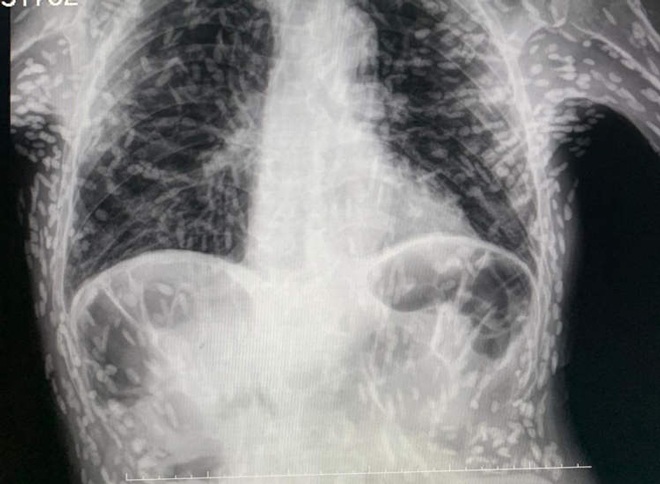

Hình ảnh phim chụp X-quang của bệnh nhân nhiễm trứng sán dây lợn.

Bác sĩ giải thích rằng những đốm trắng có thể nhìn thấy khắp phần thân trên và cánh tay của người đàn ông là trứng sán dây bị vôi hóa sau khi bị nhiễm ký sinh trùng đường ruột. Được biết nam bệnh nhân đến khám sau khi ho dai dẳng và may mắn thay khi không gặp nguy hiểm gì vì tất cả chúng đều bị vôi hóa (không thể sống được). Mặc dù trứng sán dây lợn (cysticerci) không đe dọa đến sức khỏe của người đàn ông nhưng chúng đã gây xôn xao trên mạng xã hội Brazil.

Bác sĩ de Souza giải thích trên Twitter: “Những trứng sán này bị vôi hóa, vì vậy nó không gây ra bất kỳ sự khó chịu nào, người đàn ông vẫn có thể sống bình thường”.